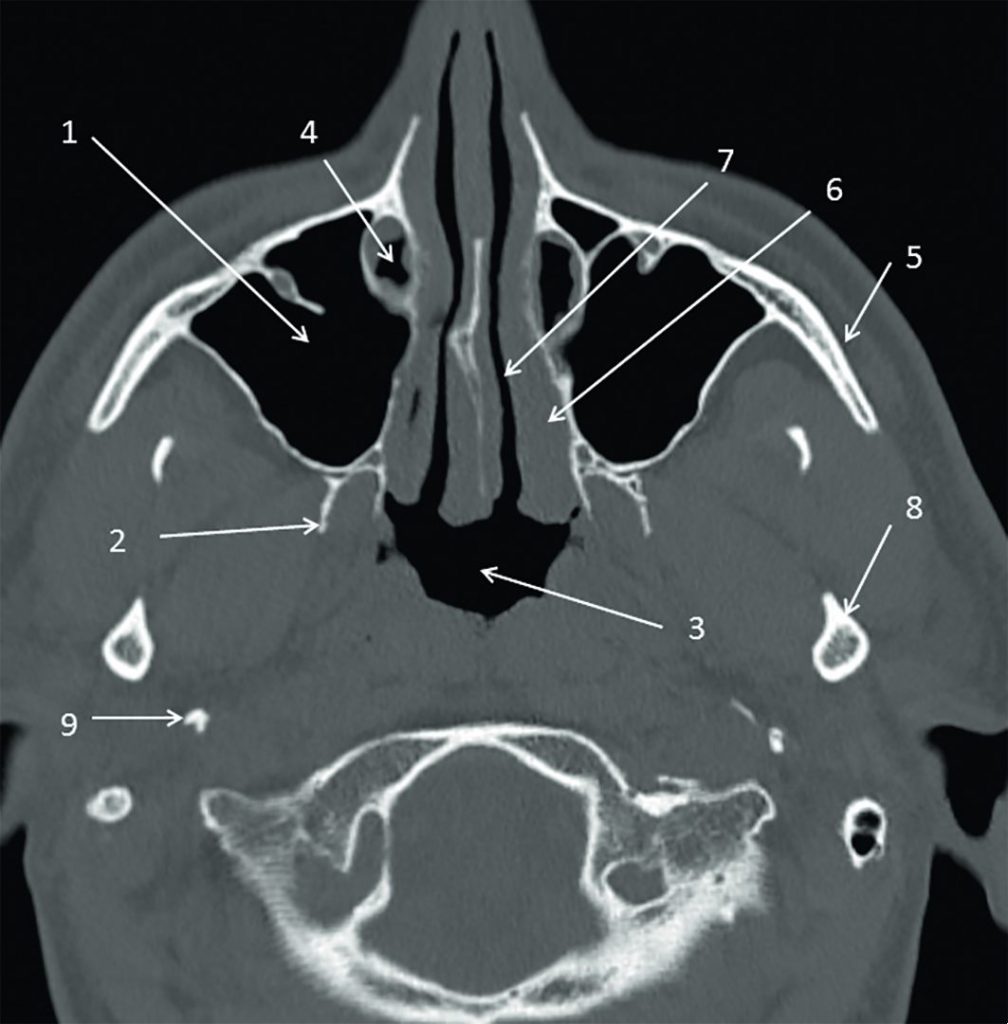

Fig. 62.5 Sinus : scanner, coupe transversale.

1. Sinus maxillaire. 2. Processus ptérygoïde du sphénoïde. 3. Nasopharynx. 4. Conduit lacrymal. 5. Os zygomatique. 6. Cornet inférieur. 7. Fosse nasale. 8. Col gauche de la mandibule. 9. Processus styloïde temporal.